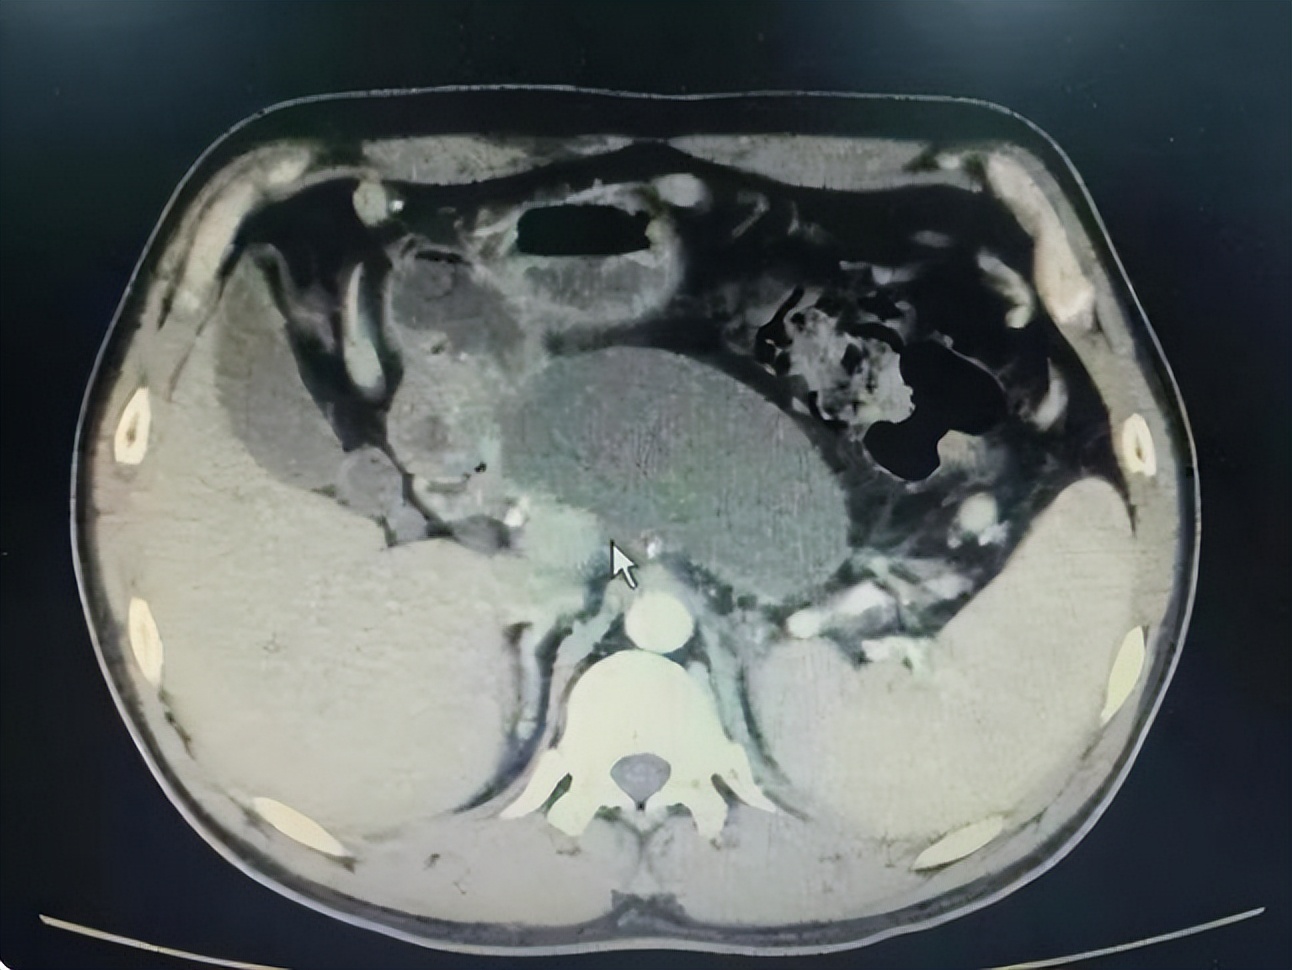

3、胰腺囊肿

胰腺囊肿包括真性囊肿、假性囊肿和囊性肿瘤,是最常见的,真性囊肿很少见如果是真性囊肿,胰腺囊肿体积小,不需要药物治疗,定期观察就好,每年至少做一次b超,如果是假性囊肿,一定要及时治疗,尤其是大囊肿,要尽早就医,如果囊肿内感染严重,会发展成脓肿,患者会出现难以忍受的腹痛,甚至导致败血症。